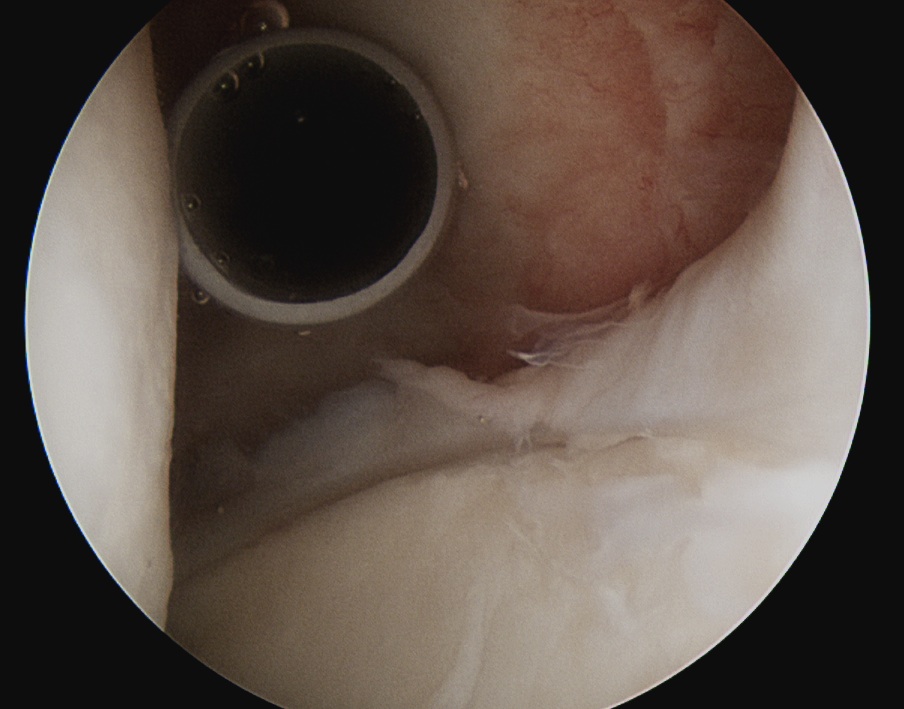

| Inferior glenohumeral ligament (IGHL) | |

|---|---|

|

Origin: Inferior 2/3 glenoid and labrum Insertion: Anatomical neck humerus

Anterior band: antero-inferior glenoid to 3 o'clock Posterior band: postero-inferior glenoid to 9 o'clock Axillary pouch between two bands |

| Most important ligament in terms of stability | Stabilizes arm at 90 degrees of abduction |

Anterior IGHL glenoid attachment |

IGHL humeral attachment |

Inferior recess

Loose body in inferior recess

Undersurface supraspinatus - abduct arm

Infraspinatus / bare area / Hill Sachs